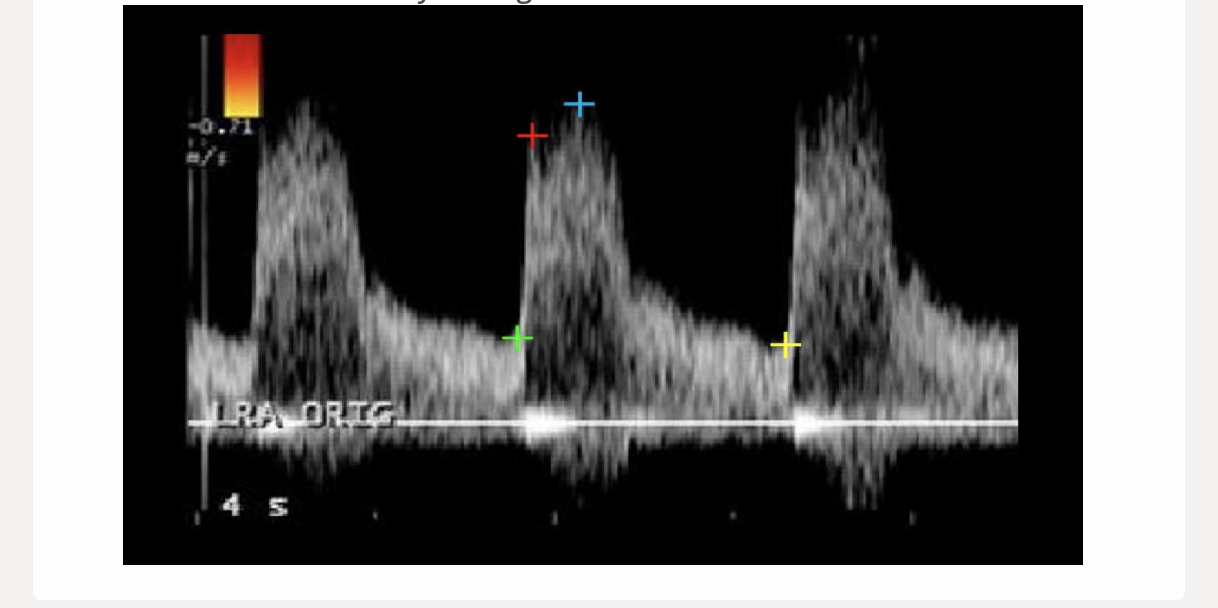

what is the proper caliper placement for assessing portal vein diameter

.

a) inner to inner wall at the junction of splenic vein + portal vein

b) outer to outer wall at the junction of splenic vein + portal vein

c) outer to outer wall where portal vein crosses IVC

d) inner to inner wall where portal vein crosses IVC

d. inner to inner wall where portal vein crosses IVC